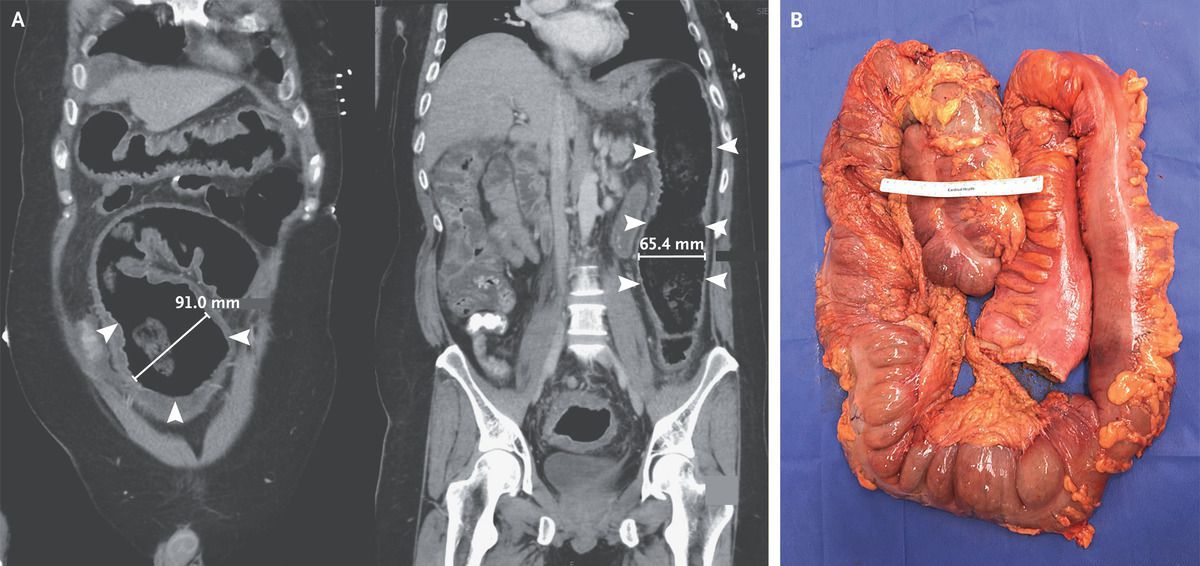

A 40-year-old man presented to the emergency department with vomiting and diarrhea. He had no known medical history and had not received antimicrobial therapy recently. His heart rate was 132 beats per minute, and other vital signs were normal. Examination was notable for confusion and for diffuse tenderness to palpation of the abdomen with tympany. Laboratory testing showed a white-cell count of 29,000 per cubic millimeter (reference range, 4000 to 10,800) and a positive nucleic acid amplification test for Clostridioides difficile. Computed tomography of the abdomen revealed pancolitis with distention of the sigmoid and descending colon (Panel A; arrowheads indicate the areas of distention, and two-dimensional measurements of colon width are shown). Despite 2 days of treatment with oral and rectal vancomycin and intravenous metronidazole, shock developed in the patient on hospital day 3. An urgently obtained radiograph of the abdomen showed worsening distention of the transverse colon near the hepatic flexure to 120 mm (abnormal width, >60 mm). Owing to concern for toxic megacolon due to fulminant C. difficile colitis, an emergency total colectomy with end ileostomy was performed. Gross pathological examination showed colonic dilatation with pseudomembranes (Panel B). Histopathological assessment showed pseudomembranous colitis, a finding consistent with C. difficile infection. The patient did well after surgery and was discharged 6 days after the procedure. Sumanth K. Bandaru, M.D. MedStar Harbor Hospital, Baltimore, MD sumanthkumar.bandaru@medstar.net source: nejm.org